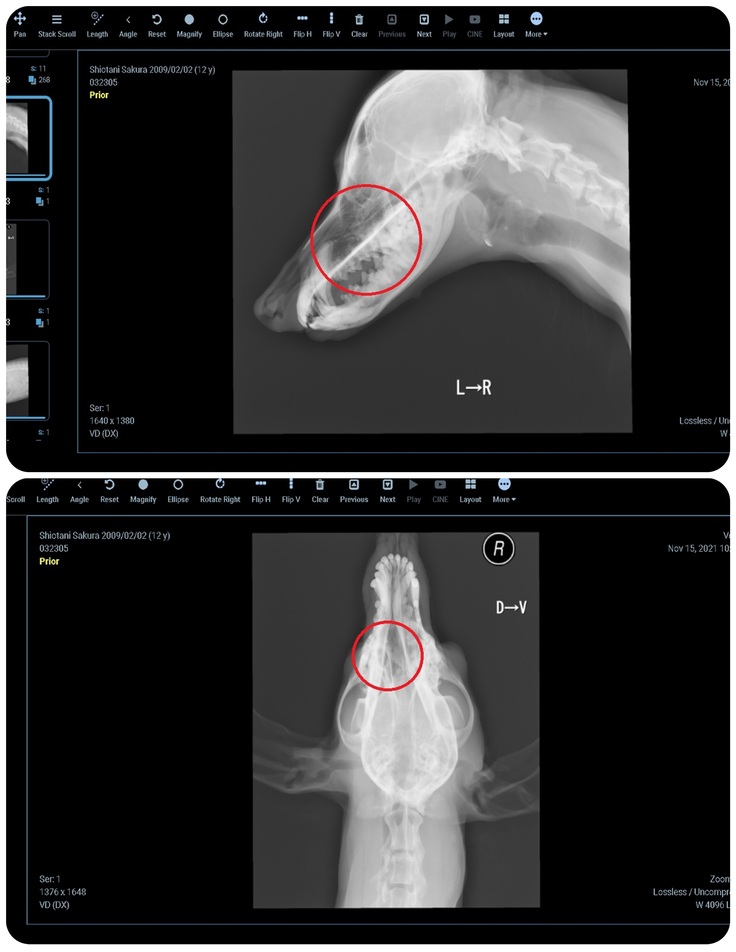

▼ 大学病院で撮ったCT画像です。赤丸の個所に腫瘍が出来ています。